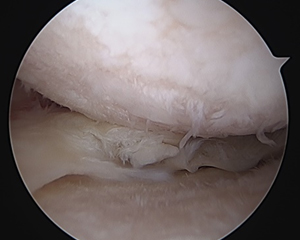

関節内遊離体切除+microfracture法

中高年者の膝の痛みの中には、投薬、注射やリハビリなどの治療を受けても効果が見られないことがあります。このような場合、半月板損傷や関節軟骨損傷(関節内遊離体)が原因になっていることがあります。半月板損傷や、関節軟骨損傷は、レントゲン検査では判明しにくいためMRI検査を行い、検査で異常が認められる場合には、小さな切り口で大きな効果が得られる関節鏡視下手術をおすすめします。

関節鏡の手術の傷は、約5mm程度のものが2か所で、ほとんど目立ちません。また入院も数日~1週間程度で、職場復帰も比較的早く可能です。